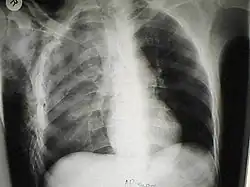

O tórax instável é uma condição médica com risco de vida que ocorre quando um segmento da caixa torácica se rompe devido a um trauma e se desprende do resto da parede torácica. Dois dos sintomas do tórax instável são dor no peito e falta de ar.

O diagnóstico é feito por exame físico realizado por um médico. O diagnóstico pode ser auxiliado ou confirmado pelo uso de imagens médicas com radiografia simples ou tomografia computadorizada. Movimentos paradoxais de segmentos manguais. Crepitação e sensibilidade perto de costelas fraturadas.